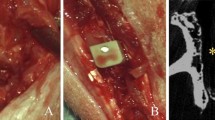

Research and development of polyetheretherketone (PEEK) composites with high thermal conductivities and ideal thermal stabilities have become one of the hot topics in composites. However, not all PEEK composites have the necessary characteristics adequate fracture toughness to resist forces and crack propagation, with an improved mechanical and structural properties. This research evaluates a novel computational surface characterisation and finite element analysis (FEA) of polyetheretherketone and hydroxyapatite graphene oxide (PEEK-HAP-GO) in the process of 3D printing to improve fracture toughness to resist forces and crack propagation. It also focuses on increasing the hydrophilicity, surface roughness, and coating osteoconductive of PEEK-HAP-GO for the bone implant. Compression and tensile tests were performed to investigate the mechanical properties of the PEEK-HAP-GO structure. The addition of calcium phosphate and the incorporation of porosity in PEEK-HAP-GO has been identified as an effective way to improve the osseointegration of bone-implant interfaces of PEEK-HAP-GO. The further analytical structure of the particle was performed, evaluating the surface luminance structure and the profile structure of composite material in 3D printing, analysing the profile curve of the nanostructure from the scanning electron microscope (SEM). The results of the uniaxial compression tests in new PEEK-HAP-GO biodegradable materials show good compressive strength suitable for loading applications. It shows melt-blending with bioactive nanoparticles can be used to produce bioactive nanocomposites like HAP-GO and is used to modify the surface structure of PEEK implants in order to make it more bioactive.

Oladapo BI, Zahedi SA, Adeoye AOM 3D printing of bone scaffolds with hybrid biomaterials. Compos B Eng 158:428–436